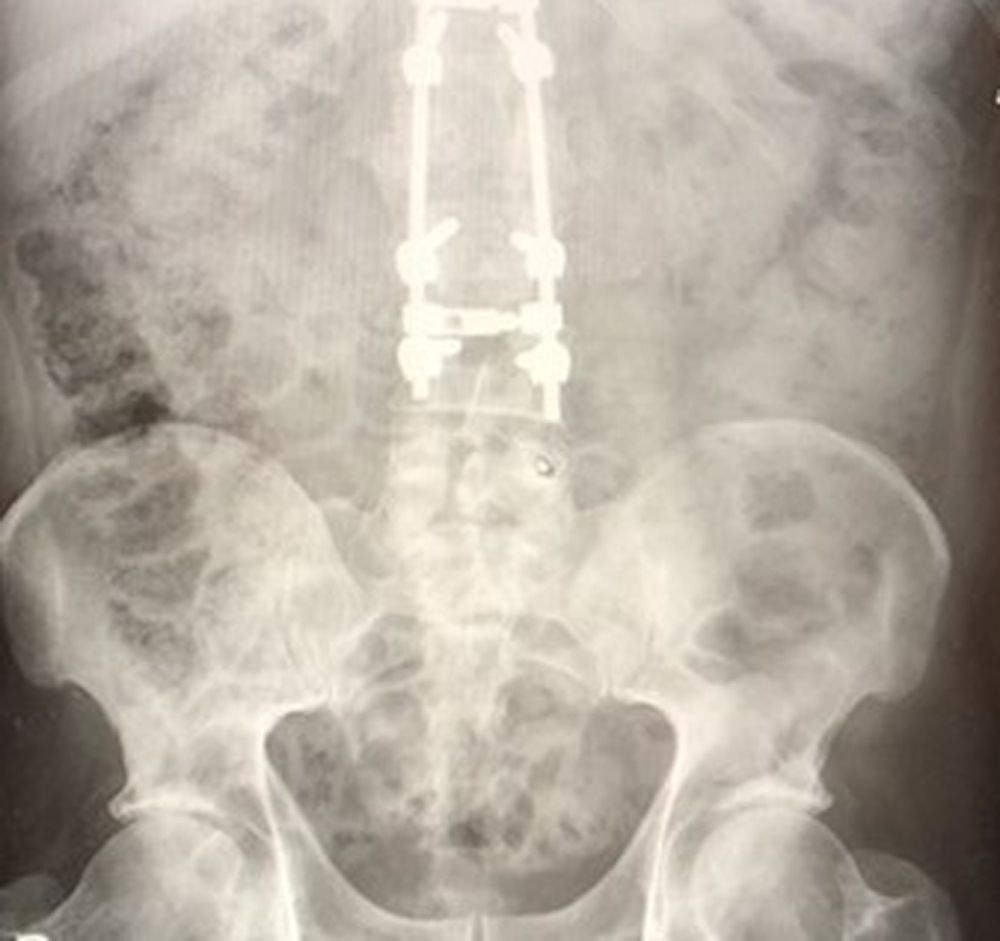

“Doctors told me I'd broken my back in four places, punctured one of my lungs, broken six ribs and ripped a major artery in my stomach, which resulted in me losing four pints of blood," he said.

“They told me they'd managed to set the spinal break with two large titanium rods, running down the middle of my back to my lower back.